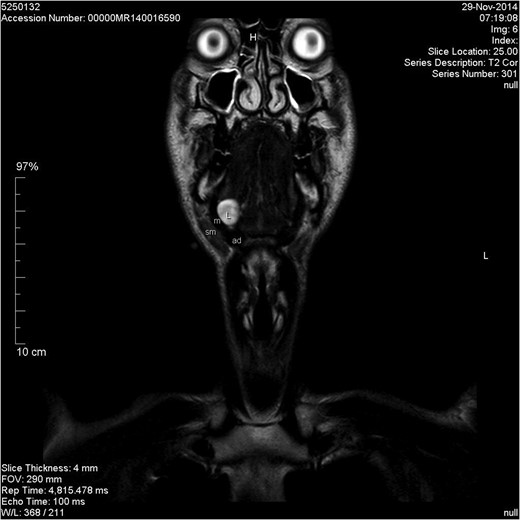

Coronal T2-weighted image. L, lesion; m, mylohyoid muscle; sm, submandibular gland; ad, anterior belly of digastric muscle.

Schwannoma is difficult to diagnose clinically but, a long-standing history and a firm mass are suggestive [4]. Radiological diagnosis can also be challenging with sensitivity estimated at 20% for computed tomography (CT) and up to 80% for MRI [5]. Ultrasonography is often used in the investigation of neck lumps. However, the appearance of a schwannoma can mimic a pleomorphic adenoma. The literature does not support the use of CT for the diagnosis of schwannoma and MRI is often preferred for better soft tissue delineation. This may aid in diagnosis and identification of the nerve of origin. Schwannomas appear hypointense on T1-weighted images and heterogeneously hyperintense on T2-weighted images [4, 6]. They demonstrate intense enhancement with gadolinium-based contrast. As demonstrated in our case, MRI can still fail to be diagnostic.

The differential diagnosis of a right-sided neck swelling is varied and includes: submandibular gland neoplasm, lymphadenopathy, plunging ranula, haemangioma and lipoma. A ranula is a retention cyst of the sublingual gland which usually occurs secondary to trauma or duct obstruction. It often presents as a bluish swelling in the floor of the mouth. The swelling can extend behind or through the mylohyoid muscle and into the submandibular space forming a plunging ranula [5]. A plunging ranula is usually associated with an intra-oral component but rarely it can present as an isolated neck swelling [5]. The pre-operative imaging of our patient demonstrated a homogenous, non-enhancing lesion involving the sublingual gland and extending into the submandibular space. The lesion did not show enhancement with contrast which is unusual for a schwannoma [8], and may be interpreted as being consistent with a cystic lesion. Both schwannomas and ranulas appear hypointense on T1-weighted images and hyperintense on T2-weighted images. As FNAC was inconclusive, a differential diagnosis of several pathologies was considered based on clinical assessment and radiological investigations. Given the characteristic MRI appearances and the failure to enhance with contrast, a pre-operative diagnosis of plunging ranula was made.